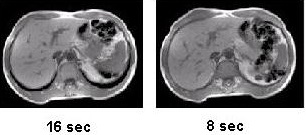

Figure 1. Abdomen without ASSET (left) and with ASSET (right)

ASSET is designed to achieve shorter acquisitions. When an ASSET acceleration of two is specified, the one-half reduction in scan time is due to every other line in k-space being skipped, while keeping the total area covered in k-space the same. When an ASSET acceleration of three is specified, the two-thirds reduction in scan time is due to every third line in k-space being filled, while keeping the total area covered in k-space the same.

When comparing two images acquired with and without the ASSET option, the ASSET image has a 50% reduction in scan time and the resulting SNR is the multiple of the square root of one-half times the SNR of the non-ASSET image. In examinations with high signal, such as a CEMRA exam, the SNR effects are rarely noticed. The actual SNR is dependent on the appropriateness of the coil to the particular use of ASSET.